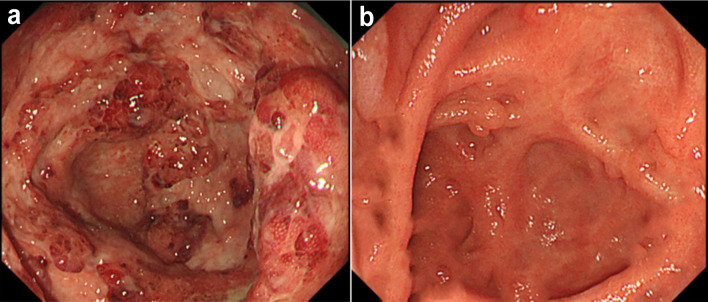

Case 1 involved a 34-year-old woman who had been diagnosed with Crohn's disease (CD) at 30 years old. After deciding to discontinue CD treatment, she was diagnosed with moderate flare-up of CD based on disease activity and endoscopic findings. Inadequate response was seen 7 days after starting oral prednisolone (PSL) at 30 mg/day, so combination therapy was started with intensive granulocyte and monocyte adsorptive apheresis (GMA) plus upadacitinib (UPA) at 45 mg/day. Twelve weeks after starting this combination therapy, clinical remission and endoscopic and histological improvements of the inflamed mucosa were achieved with no adverse events. Case 2 involved a 26-year-old man who had been diagnosed with CD at 13 years old. He was diagnosed with severe flare-up of CD based on disease activity and endoscopic findings due to loss of response to double doses of infliximab (IFX). Combination therapy was started with intensive GMA plus UPA at 45 mg/day. Twelve weeks after starting this therapy, clinical remission and endoscopic and histological improvements of the inflamed mucosa were achieved with no adverse events. The combination of intensive GMA plus UPA appears to have provided an effective therapeutic option for refractory CD in a patient with a 4-year history of CD and refractoriness to systemic corticosteroids, and in another patient with a 13-year history of CD and loss of response to IFX.